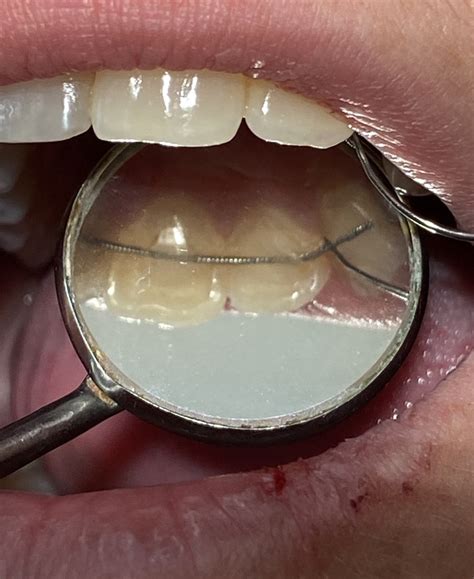

El Bond-A-Braid es un tipo de alambre que ofrece una retención permanente gracias a su diseño único. Este alambre está compuesto por 8 hilos, aplanado y blando, lo que facilita su adaptación a la superficie lingual de los dientes. Sus principales ventajas son:

- Ofrece una retención permanente.

- Evita problemas de control.

- Adaptación sencilla.